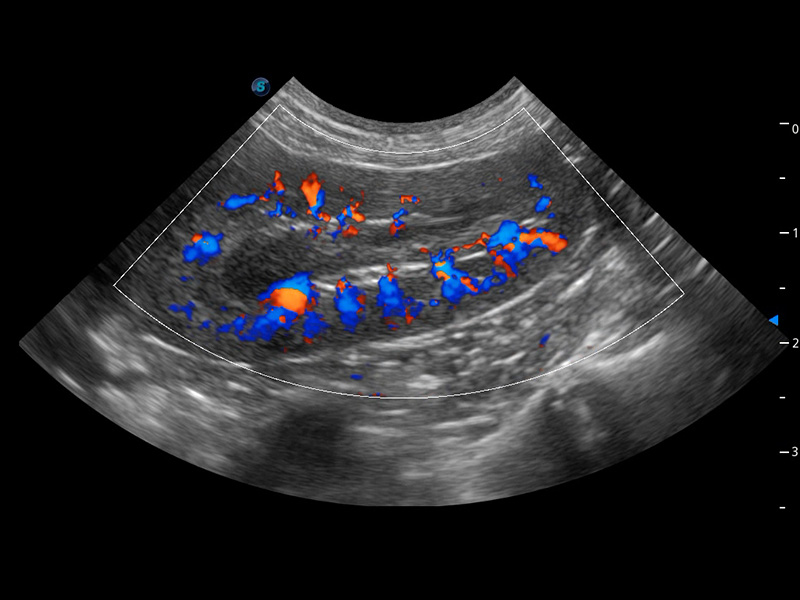

4T血流成像 微察秋毫

融合不同血流成像技术的优势,即可以提升血流成束性,同时可提高血流的视觉敏感性。

PDI 能量多普勒血流

提供高灵敏度和空间分辦率的血流图像,获得更加真实和丰富的诊断信息。

SR Flow 高分辨率血流成像

能够清晰显示细小、低速血流图像,获取传统彩色多普勒技术难以得到的细节和信息。

Micro F 显微血流成像

通过创新的Matrix E自适应滤波器和超长时间域算法,极大提升超低速微细血流的检出能力,同时更精准地滤除软组织和噪声信号,为兽用医生提供以往无法通过常规血流获得的疾病诊断信息。

优异的基础图像

(犬)肾脏血流